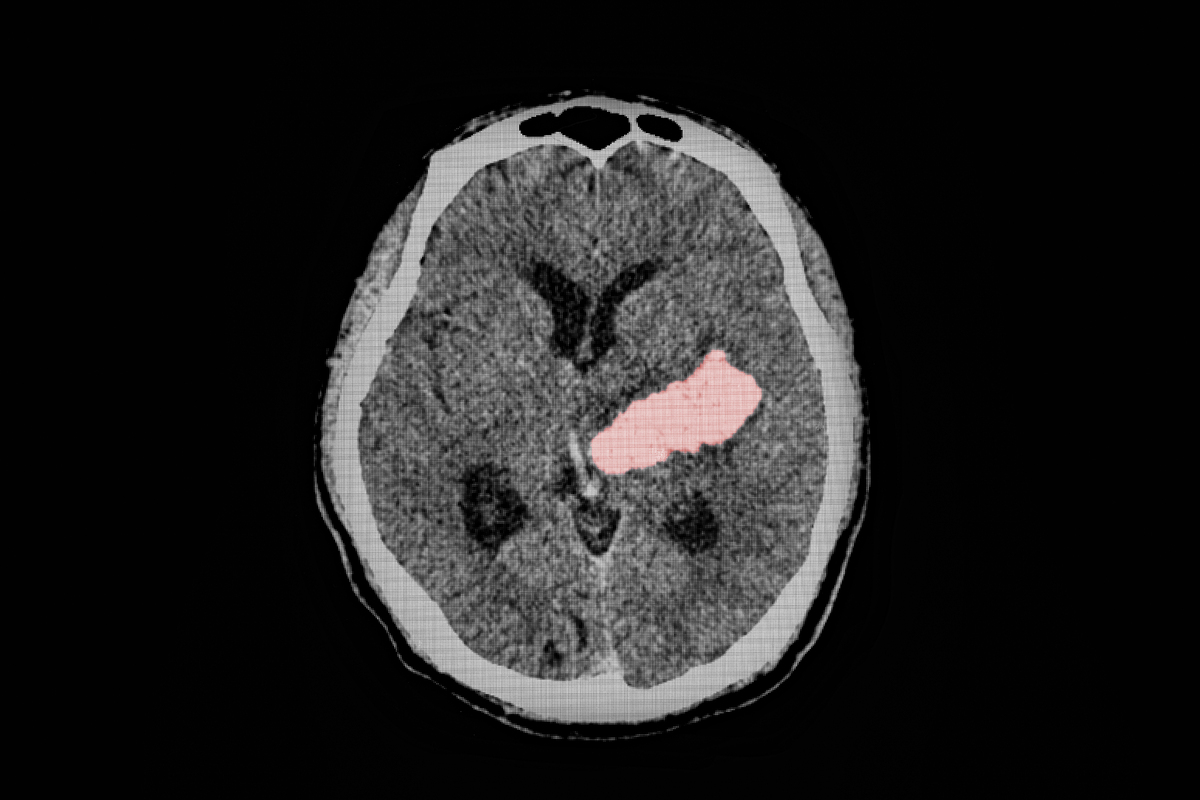

젊은 뇌졸중에는 몇 가지 특징이 있다. 첫째, 뇌출혈의 비율이 높다. 전체 뇌졸중 중 80~85%가 뇌경색이고 15~20%가 뇌출혈인데, 젊은 뇌졸중은 뇌경색이 50~60%, 뇌출혈이 40~50%에 달한다. 둘째, 발생 원인이 다양하다. 40대 이상에서는 고혈압, 당뇨병, 고지혈증, 흡연, 음주와 같은 잘 알려진 위험인자가 주된 원인이다. 그러나 20~30대 환자에서는 혈전을 잘 만드는 혈액질환, 혈관염, 경동맥이나 척추동맥의 박리, 모야모야병, 편두통, 여성의 경우 임신이나 호르몬제 복용 등이 원인이 되기도 한다. 특히 모야모야병은 뇌경색과 뇌출혈을 모두 일으킬 수 있는 질환으로 유전적 요인이 드물게 작용하는 경우도 있다.